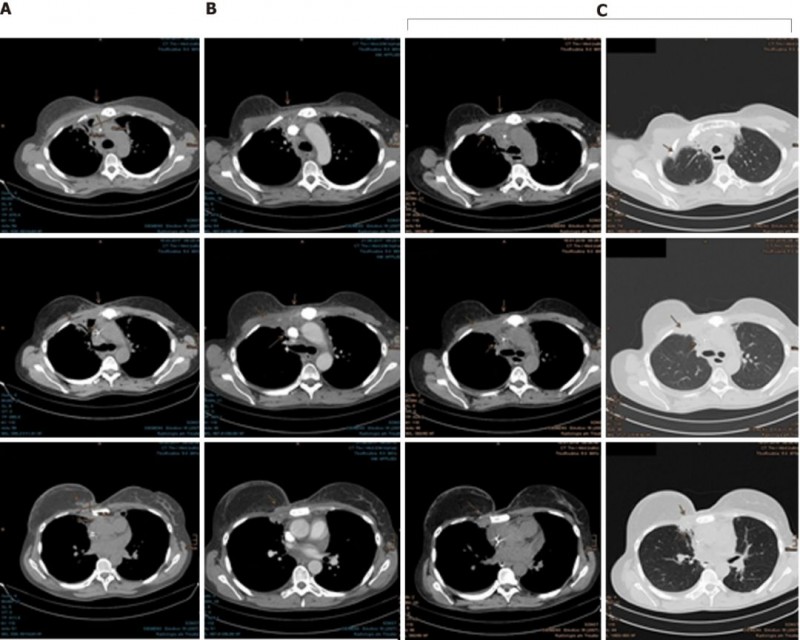

2014年5月,Mary照常复查,看到胸骨上有可疑的病灶,穿刺完却发现没有癌细胞。

2015年7月,CT扫描发现肿瘤已经侵入肋软骨和腹侧胸膜,她的癌症全面复发了。

这时,Mary已经没有更多的选择,为了降低体内雌激素水平,她切除了双侧卵巢,然后参加了一项氟维司群联合ribociclib的临床试验。2016年2月,由于病情进展,她退出了试验,右侧胸骨的病灶已经达到了30 mm×50 mm×20 mm。

幸运的是,Mary对质子治疗的耐受性很好,仅出现了轻微的咳嗽和反流。由于对肺部有一定的辐射剂量,她吃了一些环丙沙星预防放射性肺炎的发生。随后的检查结果显示,癌细胞终于耐不住质子的强烈攻击,开始节节败退,病灶在一次次的缩小。

在最近一次CT扫描中,仍然没有发现肿瘤进展迹象。为了预防病情进展,Mary现在继续使用来曲唑和denosumab进行全身治疗。